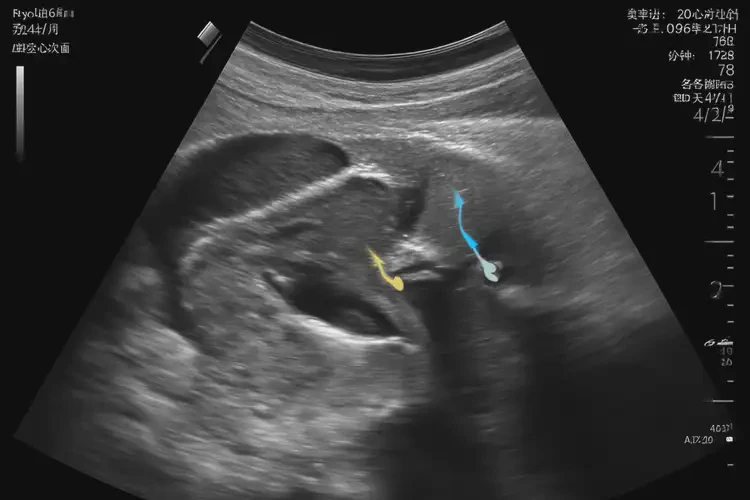

孕24周6天胎心176還能保住嗎

胎心176次/分鐘在孕24周6天仍屬正常范圍,胎兒通??梢员W?。

胎心率是指胎兒心臟每分鐘跳動(dòng)的次數(shù),正常范圍為120-160次/分鐘。在孕24周6天時(shí),胎心率達(dá)到176次/分鐘,雖然略高于正常范圍,但并不意味著胎兒無法保住。以下是詳細(xì)分析:

孕24周6天胎心176還能保住嗎(圖1)